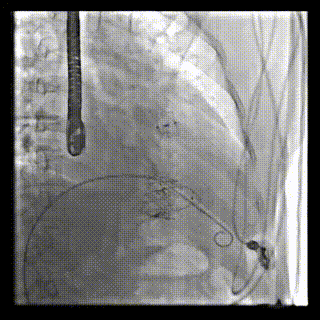

本周三例接受LuX-Valve Plus經(jīng)血管三尖瓣置換術(shù)的患者中,第一例患者為冠狀動脈旁路移植術(shù)+Bentall+二尖瓣成形術(shù)后;第二例患者為永久起搏器植入術(shù)后,存在跨三尖瓣導(dǎo)線;第三例患者合并房顫、房缺及左心耳封堵術(shù)后。

三例患者入院后,葛均波院士團(tuán)隊周達(dá)新教授、潘文志教授、張源博士、陳莎莎博士及心超室的潘翠珍教授、李偉教授對患者的情況進(jìn)行詳細(xì)評估和討論,最終決定為三例患者選擇LuX-Valve Plus40mm、50mm和50mm型號的瓣膜進(jìn)行手術(shù)治療。手術(shù)后即刻拔除氣管插管,術(shù)后患者三尖瓣反流癥狀得到顯著改善,復(fù)查心超結(jié)果顯示人工三尖瓣瓣膜支架固定穩(wěn)定,瓣葉關(guān)閉形態(tài)未見異常,未見明顯反流。